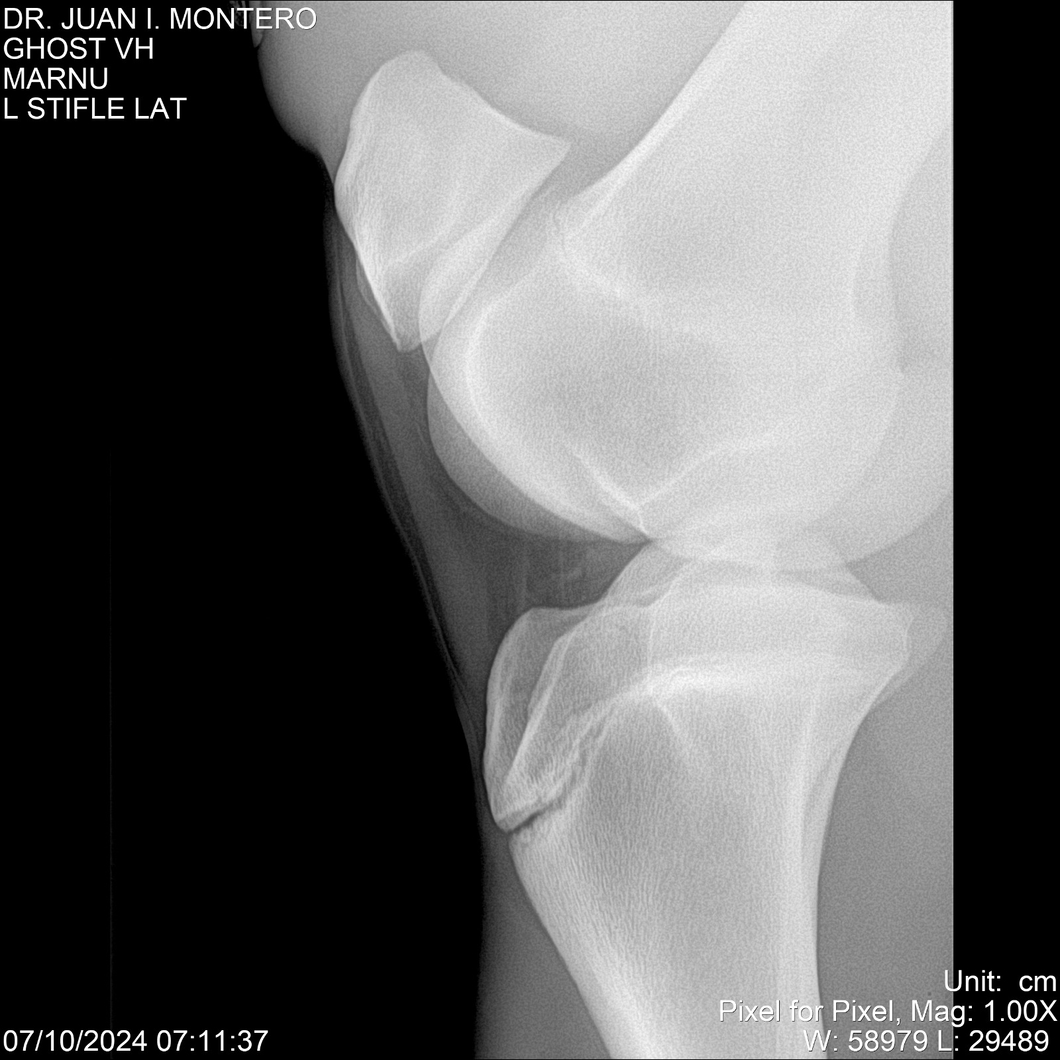

LOTE 15, GHOST VH 🔥 🔥 🔥 Lote Anterior Volver al remate Lote Siguiente Ficha Contacto Montevideo - Ficha del Lote Identificador: #282525 Categoría: Yeguarizos Montevideo - 69 Visualizaciones ClicData Contacto Empresa: Abelenda N. R., Walter Hugo Nombre*: Teléfono* : E-mail* : Mensaje Enviar Registrese gratis Este contenido Exclusivo está disponible sólo para usuarios registrados Ingresar